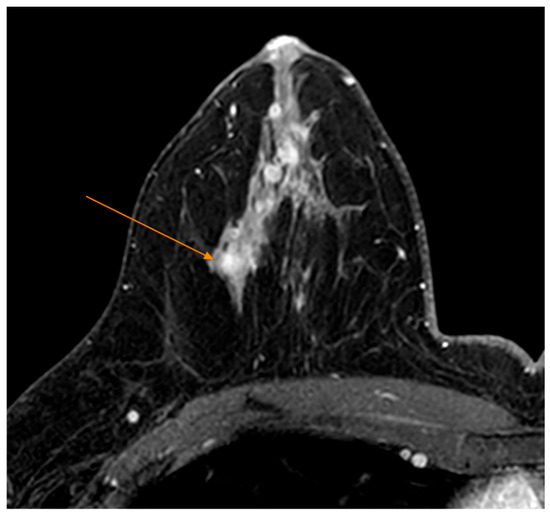

Tumors were classified using the WHO histologic criteria (such as invasive ductal carcinoma, invasive lobular carcinoma, ductal carcinoma in situ, and mixed histology). Age categories were used for analysis. Advanced imaging methods such as breast ultrasound (Figure 2), MRI (Figure 3), mammography (Figure 4), or CT were performed in only a subset of patients, highlighting significant shortcomings in early detection and screening practices within the healthcare system.

Figure 3. MRI Examination—T1 FS Sequence Post IV Contrast—Nodular mass-like contrast enhancement, located deep in the right breast gland, external quadrant (arrow).